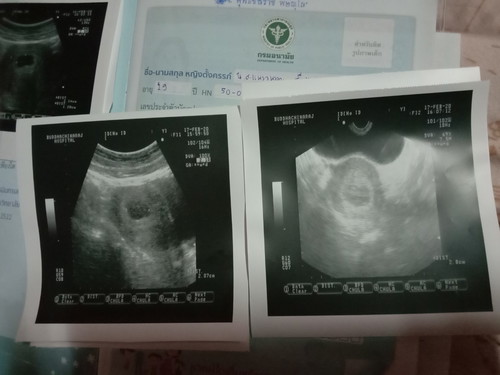

ท้อง1เดือนกว่าๆ

อยากทราบว่า อายุครรภ์ กี่สัปดาห์ถึงจะเห็นตัวลูกคะพอดีเป็นท้องแรกค่ะ ตอนนี้ 6 สัปดาห์แล้ว ยังอัลตร้าซาวด์ไม่เจอน้องเลยค่ะเลยกลัวจะเป็นท้องลมค่ะ

บ้านนี้เห็นตอน 8w ค่ะ